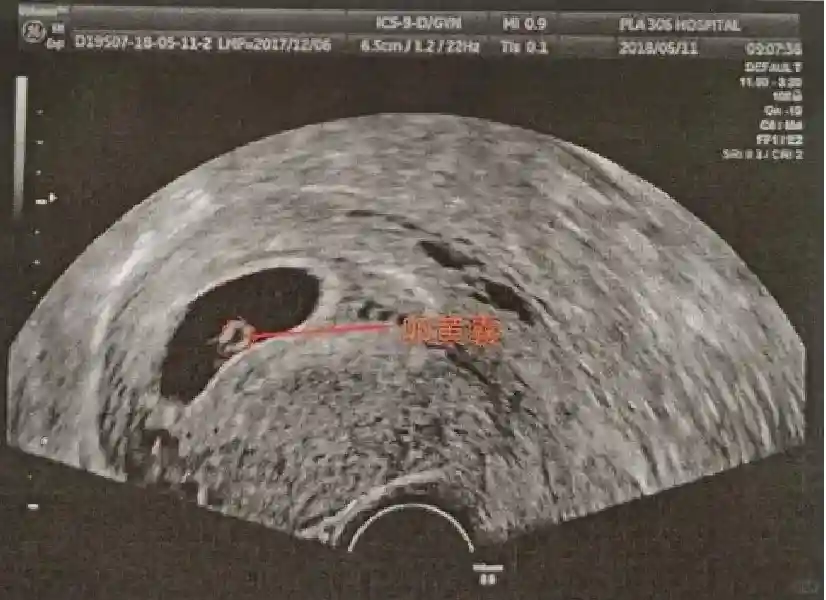

2️⃣卵黄囊:是妊娠囊内第一个解剖结构,直径<7mm。表现为小环状,中央为无回声,囊壁薄,内透声好。卵黄囊位于胚胎旁胚外体腔内。卵黄囊通常在孕5-6周时出现,5-10周稳步增长,一般不超过7mm,至12周消失。妊娠囊的大小与卵黄囊之间有一定关系,妊娠囊平均直径> 8 mm 时,经阴道超声均应显示卵黄囊,妊娠囊平均直径> 18 mm 时,经腹超声均应显示卵黄囊。